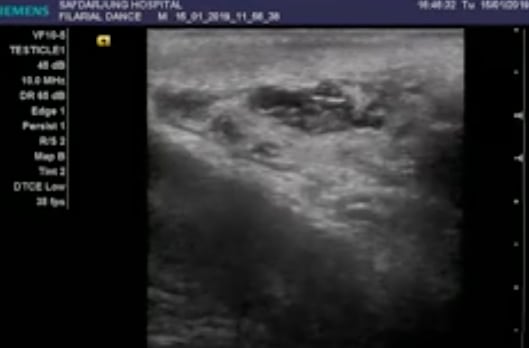

En ellas se aprecia a los gusanos en movimiento dentro de un canal linfático dilatado del testículo; tubos delgados que transportan líquido y glóbulos blancos en el escroto.

Durante el examen, los profesionales detectaron sensibilidad e hinchazón en el lado derecho del escroto, y una ecografía posterior mostró a los gusanos bailando en el interior de su testículo.

Asimismo, con las ondulaciones de gusanos vivos que han migrado a los canales linfáticos, se experimenta dilatación y disfunción en el testículo.